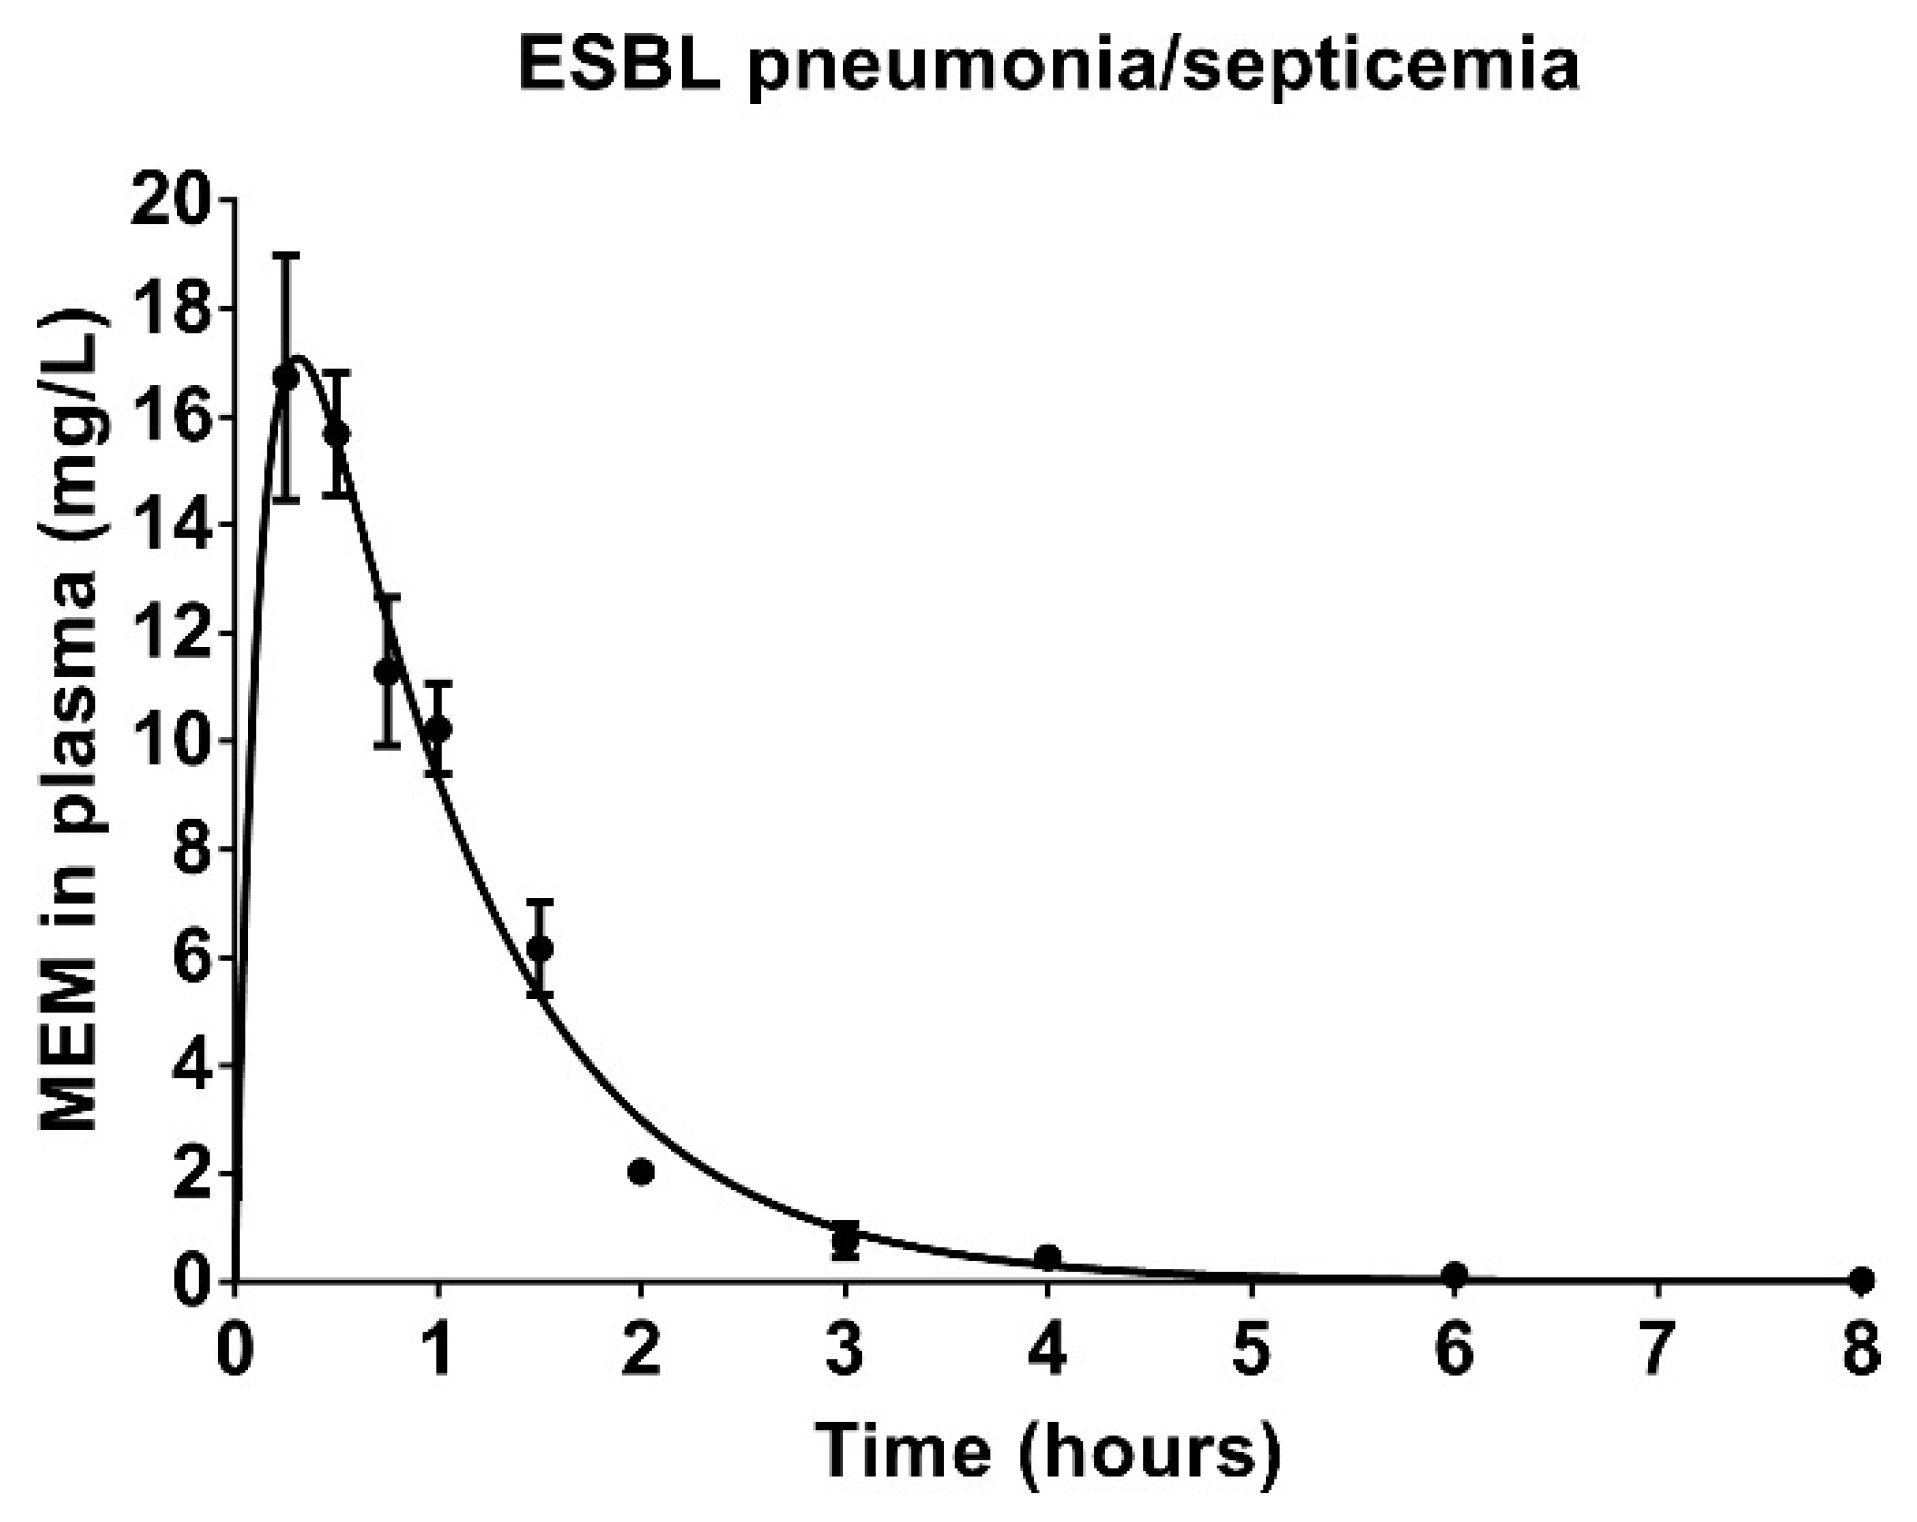

3.6. Pharmacokinetics of Meropenem in Rats with ESBL Pneumonia–Septicemia

| Pharmacokinetic Parameter | V/F | CL/F | t1/2 | ƒCmax | ƒT > MIC | |||

|---|---|---|---|---|---|---|---|---|

| 0.063 mg/L | 16 mg/L | |||||||

| L/kg | L/kg/h | h | mg/L | h | % | h | % | |

| Estimate | 1.03 | 1.17 | 0.61 | 13.37 | 5.18 | 43.17 | 0.00 | 0.00 |

| SEM | 0.07 | 0.06 | 0.03 | 1.43 | 0.24 | 2.00 | 0.00 | 0.00 |